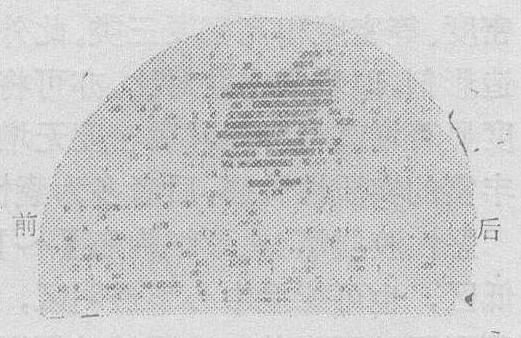

❹113mIn-DTPA从放射核素113In“发生器”中获得,可很快从血液中清除,由肾脏排出,5小时内清除达75~80%,适合于体外扫描(图2ab)。母体113In的半衰期为118天,因此“发生器” 只需3~4个月更换一次,在静脉注射后必须立刻扫描,超过40分钟,可因计数率低,影响扫描结果。

图2a 后前位右额顶枕脑膜瘤113mIn-DTPA3mCi

图2b 右侧位,同上